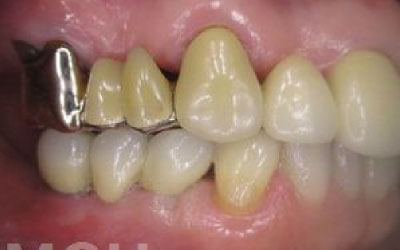

ブリッジとインプラントでは、前後の歯の寿命に大きな違いがあります。ブリッジでは、支えとなる歯を虫歯がなくても大きく削る必要があり、さらに噛む力が通常の1.5倍かかるため、その寿命が短くなりがちです。実際の統計によると、ブリッジの支えとなる歯の68%が、10年以内に抜歯を余儀なくされるという結果が出ています。

噛むとき、誰でも歯に何十キロもの力がかかっています。当然、歯の本数が減れば減るほど、残った歯にかかる負担は大きくなります。ブリッジ治療の場合、失われた歯にかかっていた力は、前後の歯で支えることになります。その結果、残った歯には、抜歯していないときに比べて1.5〜2倍程度の力がかかることになります。

ブリッジなどの治療では、前後の歯を大きく削る必要があります。場合によっては、虫歯がないのに歯の神経を取らなければならないこともあります。実際、神経を取って被せ物をすると、その歯は一気に「最終段階」に進んでしまうのです。しかし、インプラント治療では、前後の歯を削ることも、神経を取ることもありません。歯の寿命を延ばすためにも、健康な歯をできるだけ削らないことが非常に重要なのです。

残っている歯を守るという観点から見ると、ブリッジをしてからインプラントに移行するのは、あまりおすすめできない治療の流れです。

というのも、ブリッジをする際には両隣の健康な歯を大きく削る必要があり、場合によっては神経を取る処置まで必要になることがあります。

これにより、削った歯への負担が大きくなり、結果としてその歯の寿命が短くなってしまうのです。

将来的にインプラントを検討しているのであれば、最初からインプラントを選んだ方が、歯へのダメージを最小限に抑えられる、より良い選択といえるでしょう。

最も大きな違いは、前後の歯の寿命に影響が出ることです。

ブリッジの場合、抜けた部分の前後の歯を大きな虫歯と同じくらい削る必要があります。

また、抜けた歯の力を前後の歯が支えているため、ブリッジを支える歯には常に1.5倍の負担がかかることになります。